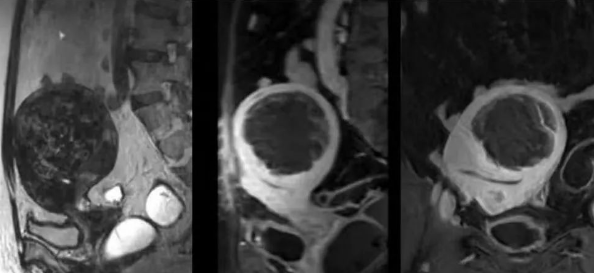

近日,西安國際醫(yī)學中心醫(yī)院影像診療中心陳寶瑩主任采用磁波刀技術為患者消融了七公分的子宮肌瘤。

陳寶瑩主任首先給祝女士進行了詳細的盆腔磁共振評估,發(fā)現(xiàn)子宮肌瘤比較大,直徑七公分,類型和位置都適合做磁波刀治療。陳寶瑩主任立即為她制定了個性化治療方案,并為她完成幾項術前檢查。

治療當天,為緩解祝女士的緊張心情,陳寶瑩主任和她進行了充分溝通。術前準備就緒后,治療正式開始了。治療過程中,患者全程清醒,可以及時反饋治療感受。醫(yī)生也即時調整,確保整個治療安全有效,兩小時后治療順利結束,患者體驗度好。即時評估發(fā)現(xiàn)7公分的子宮肌瘤被消融掉80%,達到了預期目標。祝女士觀察一個小時后,沒有什么不舒服即回家了。